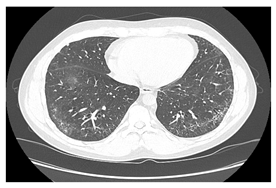

| Type of SARD-ILD | HRCT Features | Axial HRCT Images in Patients with SARD-ILD | Description of HRCT Images in Patients with SARD-ILD |

|---|---|---|---|

| SSc-ILD | NSIP, UIP with straight-edge sign and/or “four corners” sign. | ![]() | NSIP, which is the most common appearance in patients with SSc-ILD, is characterized by reticular opacities arranged in bands that run parallel to the lung’s subpleural contour, with a tendency to avoid the subpleural area. |